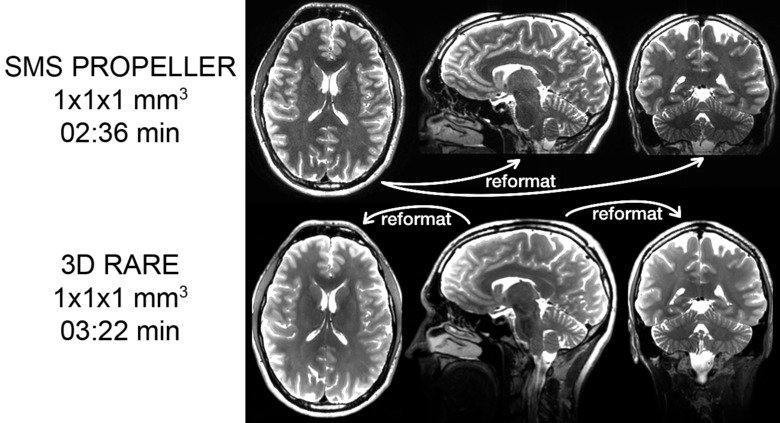

Rörelserobusta pulsesekvenser - Accelererad pseudo 3D PROPELLER

Det finns ett kliniskt behov av T2w 3D RARE/FSE/TSE bilder med isotropa voxlar som kan reformateras till flera olika blidplan. Det ökar informationen för radiologen och underlättar granskningen av bilderna. De sekvenser som typiskt används för att samla in dessa 3D dataset kräver långa ekotåg, vilket gör dem känsliga för rörelser och leder även till så kallad “T2-blurring”. För att få reformaterbara T2w volymer även för patienter som inte kan ligga stilla har vi tagit fram ett rörelserobust alternativ, som genom en kombination av SMS acceleration, tunna snitt och en PROPELLER-insamling. Den har också fördelen att den T2w kontrasten blir bättre (mer lik 2D TSE)